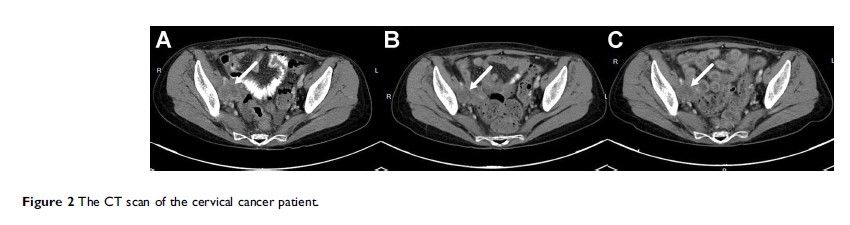

关于阿帕替尼治疗晚期宫颈癌的一项 6 例患者的回顾性研究